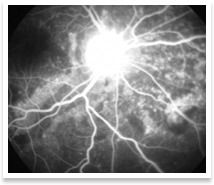

This refers to inflammation within the eye ball. It can involve the anterior portion of the eye(iritis, iridocyclitis or anterior uveitis), the middle portion of the eye(vitritis, intermediate uveitis or pars planitis) or the back portion of the eye(retinitis, retino-choroiditis or choroiditis or posterior uveitis) or the optic nerve, which carries visual information from the eye to the brain(optic neuritis). In many cases, the exact cause cannot be determined. Treatment consists of systemic steroids. Recent advances in ocular disease management enable us to give steroid injections around the eye or even within the eye itself. This has the advantage of avoiding bodily complications of systemic(tablets or intravenous injections) steroids

Uveitis can lead to other complications such as cataract, glaucoma and retinopathy or retinal detachment